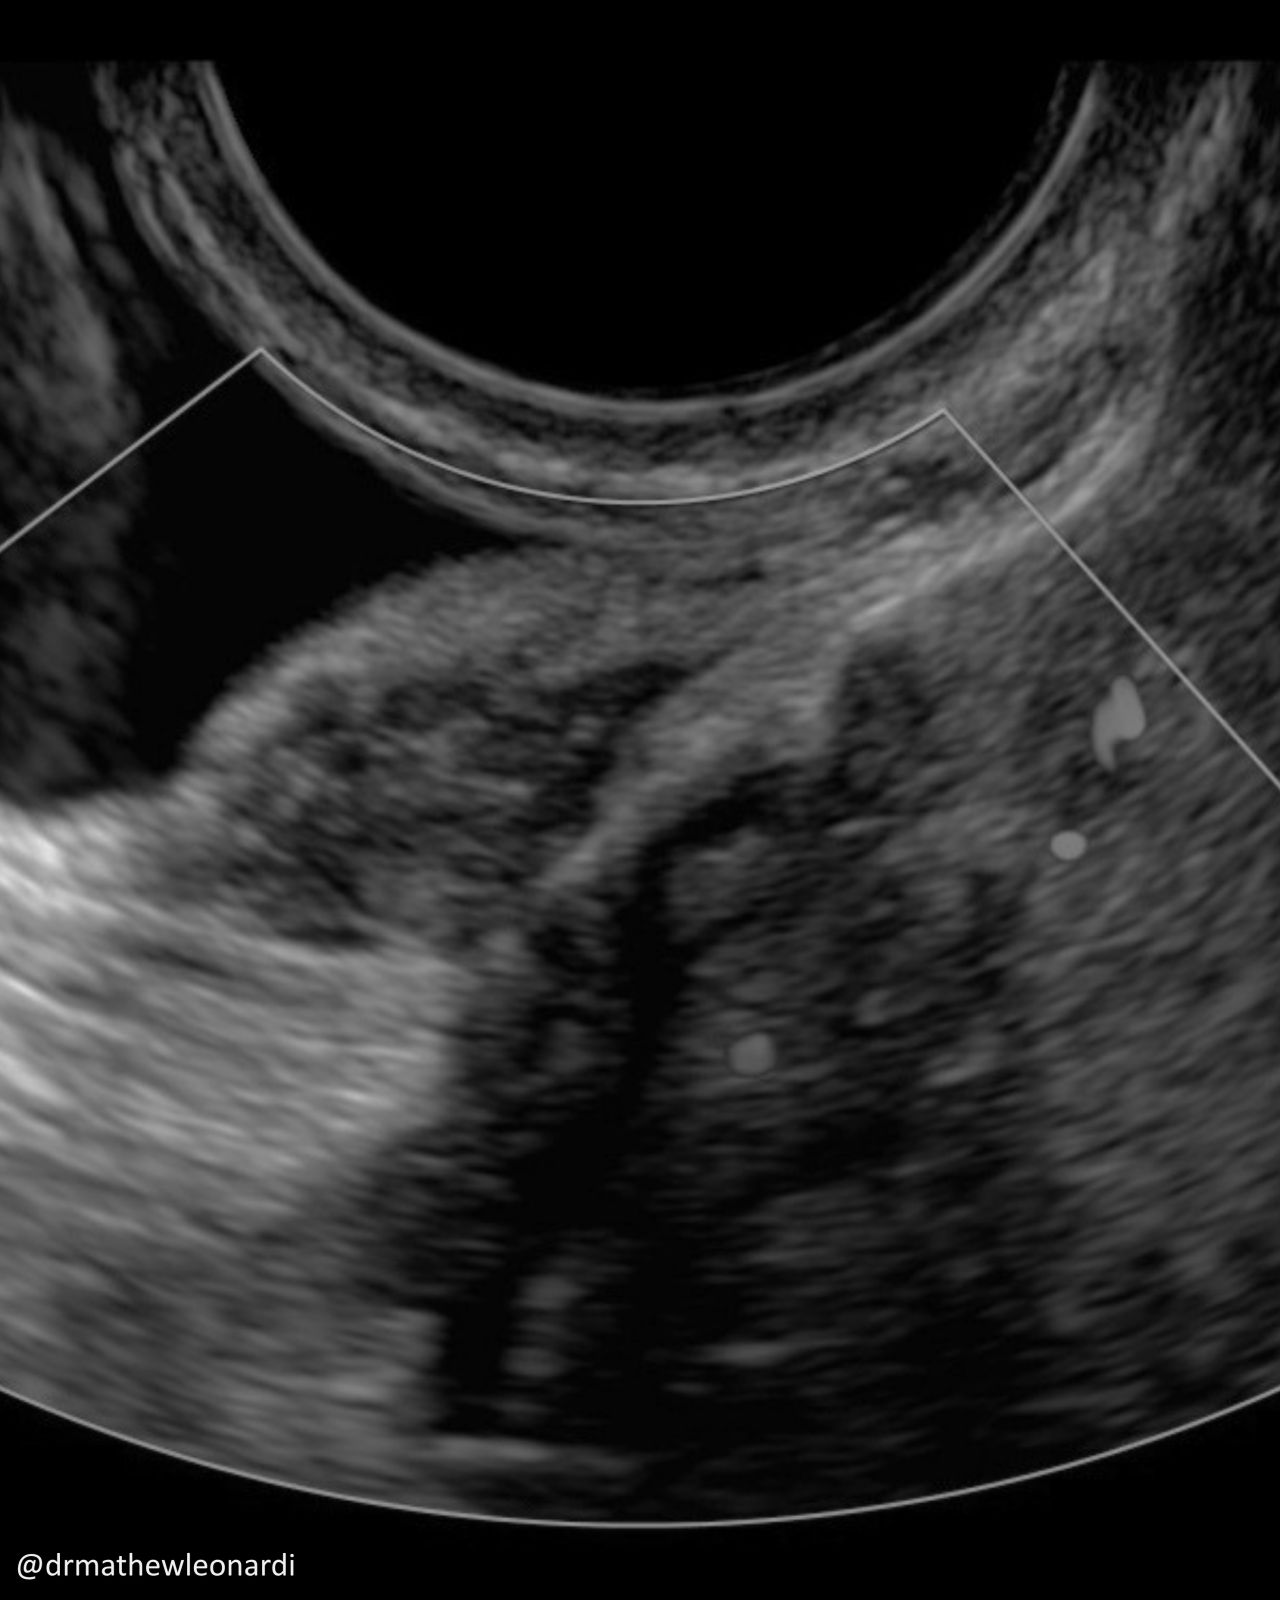

“Endometriosis does not have one single appearance, and that is part of why it is so often missed.

In this carousel, I’ve included a range of endometriosis lesions across different disease types and locations, including superficial disease, ovarian disease, and deep endometriosis involving areas such as the bowel, bladder, uterosacral ligaments, peritoneum, vagina, and ovary. A few are deliberately difficult because real-life recognition is not always straightforward.